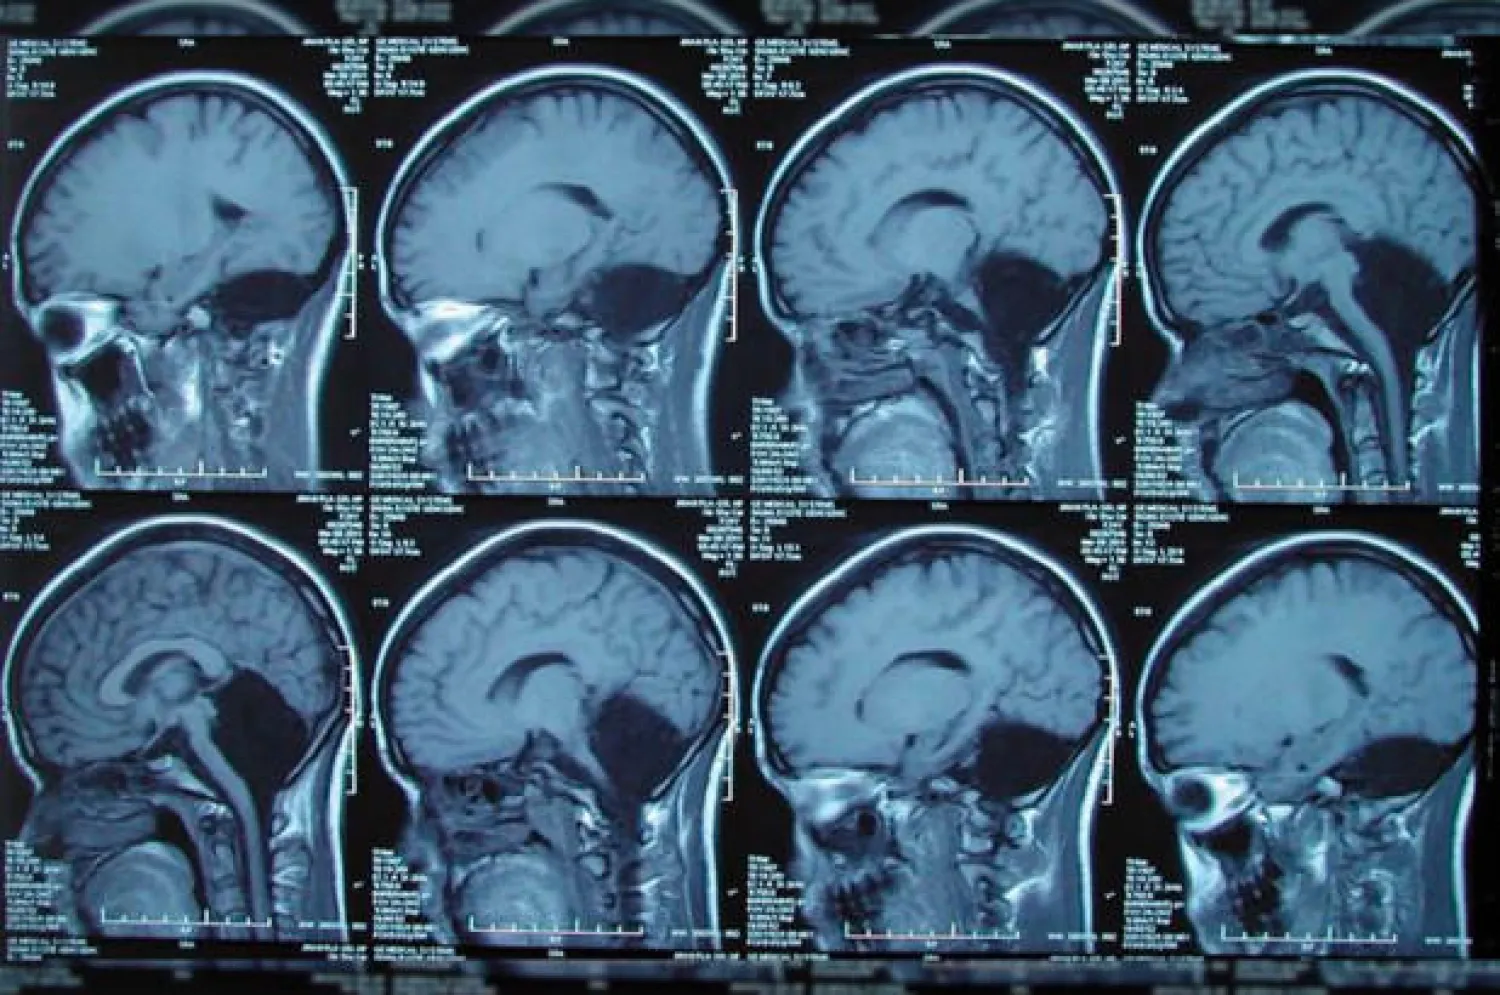

صور الأشعة المقطعية الخاصة بالشابة الصينية (نيويورك بوست)